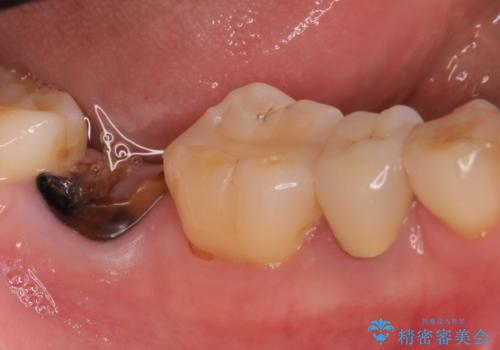

右下の奥歯を抜歯 インプラント治療による咬合回復

- 右下の奥歯をかぶせ物がとれたまま放置しているところに歯を入れたいとのことで来院されました。

精査すると保存が難しいため抜歯をして、インプラントを埋入、かぶせ物を装着する計画としました。

インプラント治療により、周りの歯を削ることなく咬合を回復することができました。